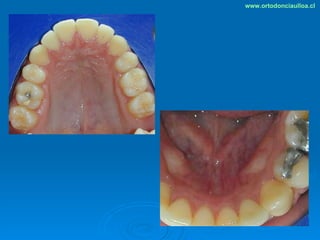

Este documento presenta dos casos clínicos de pacientes que recibieron tratamiento de ortodoncia. El primer caso fue de una paciente femenina de 14 años con apiñamiento dental y mordida cruzada que fue tratada mediante extracción de premolares y alineamiento dental. El segundo caso fue de un paciente masculino de 14 años con clase II esqueletal y desarmonía dentomaxilar que fue tratado con extracción de premolares y corrección de mordida. Ambos casos mostraron mejoría después de 3 años de tratamiento.